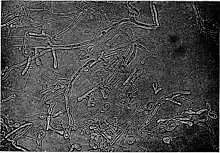

Blastomyces is a genus of fungi in the order Onygenales. Species are known human pathogens and show thermal dimorphism, converting from hyphal states under saprobic conditions to yeast-like states under pathogenic conditions. They are the causative agents of blastomycosis, a systemic mycosis in immunocompromised patients.[1][2]

| Blastomyces dermatitidis | |